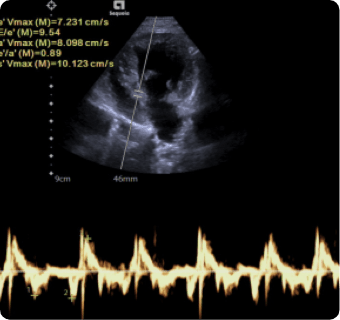

일산시티동물의료센터는 지멘스에서 개발한 고성능 프리미엄 초음파 장비인

Siemens Sequoia를 활용하여 심장, 복부 장기, 림프절 등의 구조물을 선명하게 구현하고,

이 장비는 대표적인 심장 질환인 이첨판 폐쇄부전증과 비대성 심근병증,

그리고 선천성 심혈관 질환인 동맥관 개존증, 심방중격결손, 심실중격결손 등을

진단하는 데 사용됩니다.